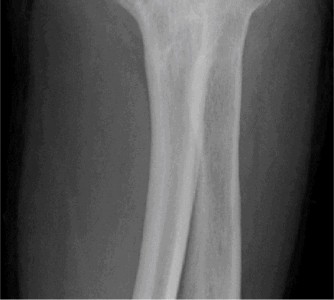

Examination reveals deformity about the elbow with no open lesions or skin tenting. He has a palpable radial and ulnar pulse and is neurologically intact. His images are shown (Figs. 2–85 to 2–88).

Figure 2–85

Figure 2–86

Figure 2–87

Figure 2–88

What is the diagnosis and direction of displacement?

- Monteggia fracture dislocation, posterolateral displacement of the forearm about the humerus

- Simple elbow dislocation, posterolateral displacement of the forearm about the humerus

- Transolecranon complex elbow dislocation

- Simple elbow dislocation, posteromedial displacement of the forearm about the humerus

Discussion

The correct answer is (B). This is the most common type of elbow dislocation, and often does not cause any osseous injury. Posterolateral and posteromedial dislocation account for approximately 90% of dislocations. Adequate pre- and postreduction films are necessary to evaluate for fracture, which would change the classification to a complex injury.